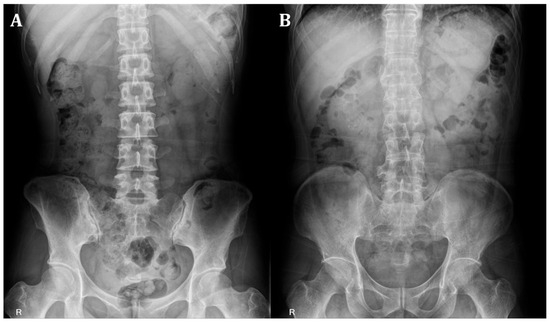

The images in Figure 3 show the regions of interest and corresponding heatmaps. This representation effectively highlights variations in data intensity across the regions of interest, facilitating an intuitive visual assessment. The heatmap colors delineate the intensity of model attention or activation within the region of interest. Warmer colors, such as red and orange, highlight areas of high importance that significantly influenced the model’s prediction. In contrast, cooler colors, like blue and purple, indicate regions of lower importance with minimal impact on the outcome.

Figure 3. Region of interest and heatmap images. The heatmap colors delineate the intensity of model attention or activation within the region of interest. Warmer colors (red and orange) highlight areas of high importance that significantly influenced the model’s prediction. Cooler colors, (blue and purple) indicate regions of lower importance with minimal impact on the outcome.